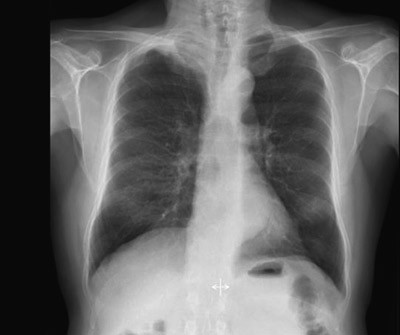

Røntgen thorax (fig 1) tatt rutinemessig ved innkomst viste en oppfylling i høyre lungetopp. CT collum/thorax/abdomen avdekket en ca. 6 cm stor svulst apikalt i høyre lunge (fig 2a, b). Det var ingen tegn til patologisk forstørrede lymfeknuter eller andre svulster. Bildene viste i tillegg emfysemforandringer og et stort abdominalt aortaaneurisme.

Fire uker etter avsluttet behandling ble pasienten reinnlagt til operativ behandling med kurativ intensjon. Ny MR collum/thorax viste fortsatt sannsynlig innvekst i 2. og 3. høyre costa samt mulig tumoraffeksjon av Th 2. Det var ikke tegn til affeksjon av plexus brachialis. CT viste at tumor hadde skrumpet (fig 2c, d). Det ble også utført PET-CT (fig 4). Denne var uegnet til vurdering av lokale forhold pga. pasientens nylig gjennomgåtte strålebehandling, men viste ingen tegn til viabelt tumorvev i thoraxveggen eller malignitet andre steder i kroppen. Basert på PET-CT-funnene ble pasienten etter tverrfaglig vurdering bedømt som operabel, og det ble gjennomført lobektomi av høyre overlapp.